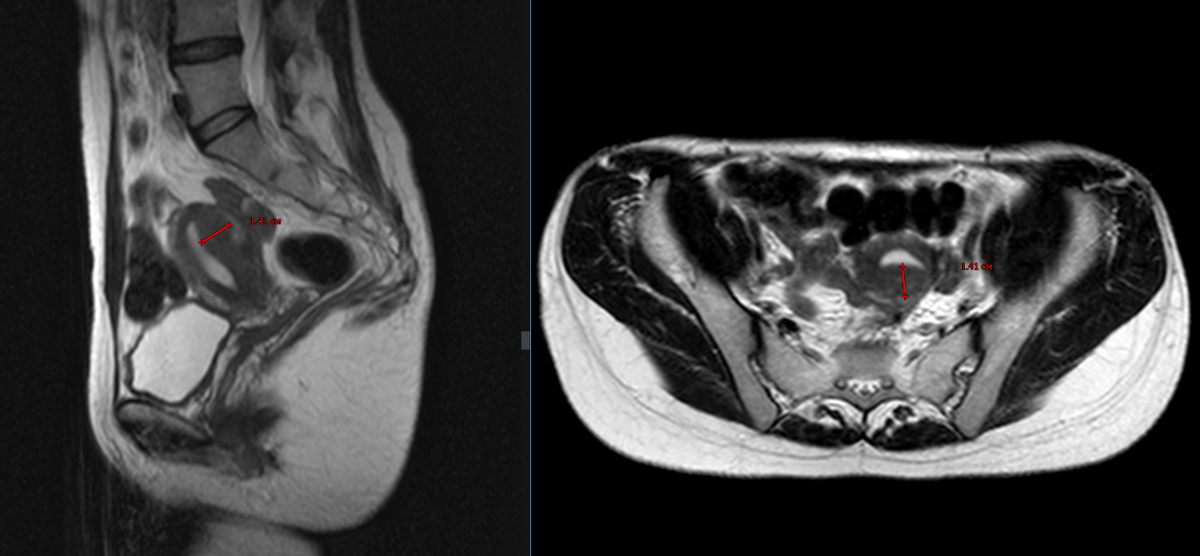

Переходный слой миометрия по задней стенке неравномерно утолщен до 1,4 см, контуры его на границе с миометрием нечеткие, внутренний контур (на границе с эндометрием) четкий, ровный, структура однородная (Рис. 1).

Рис.1: Т2 в сагиттальной (слева) и аксиальной (справа) плоскости. Утолщенный переходный слой до 1.4 см